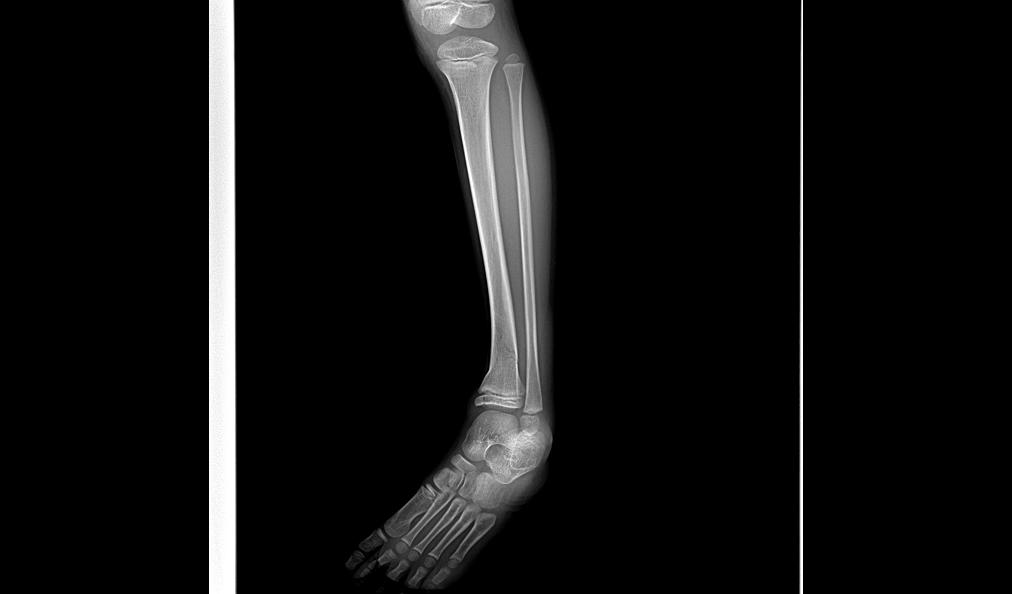

儿踝

治疗前

治疗后

骨折